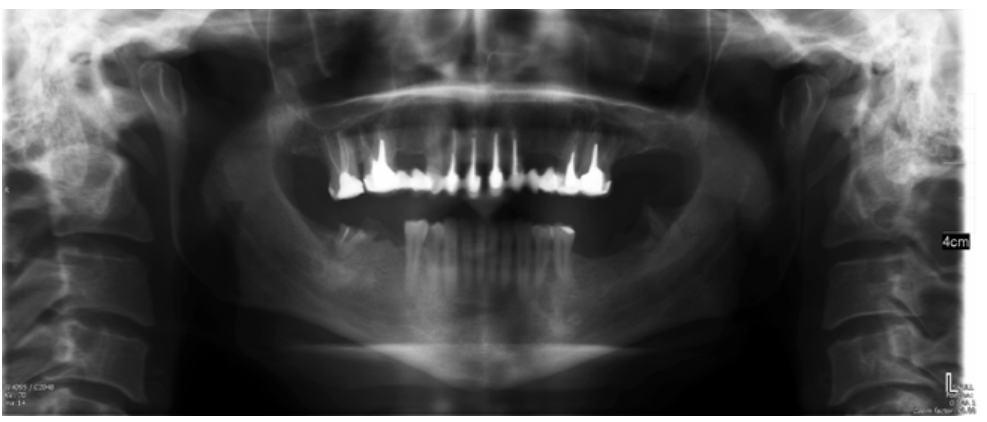

The patient provided an orthopantomography (OPG) as a radiological study (Figure 1). Periapical radiographs (Figures 2 and 3) were performed and a clinical examination including periodontal assessment of the affected teeth, without observing increased probing depths that could indicate the existence of endoperiodontal lesions.

To confirm the endodontic origin and the size of the lesions, tomographic examinations were performed with a slice thickness of 75 microns using CBCT CS8100 (Carestream Dental™), in which radiolucent periapical lesions were observed at the level of 12, 11, 21 (with bicortical involvement), 25 and vestibular roots at 26 (Figures 4 to 8).

For proper diagnosis of radiolucent lesions at the periapical level, it is important to have radiological images that accurately show their location and size. In our case, the patient provided an orthopantomography; however, this type of radiography is not suitable for diagnosis in endodontics. The periapical radiography provides better definition, especially at the anterior level, as it is less distorted. CBCT is currently the most reliable radiological test, since it provides 3D images, which help to give a more accurate diagnosis1,2.